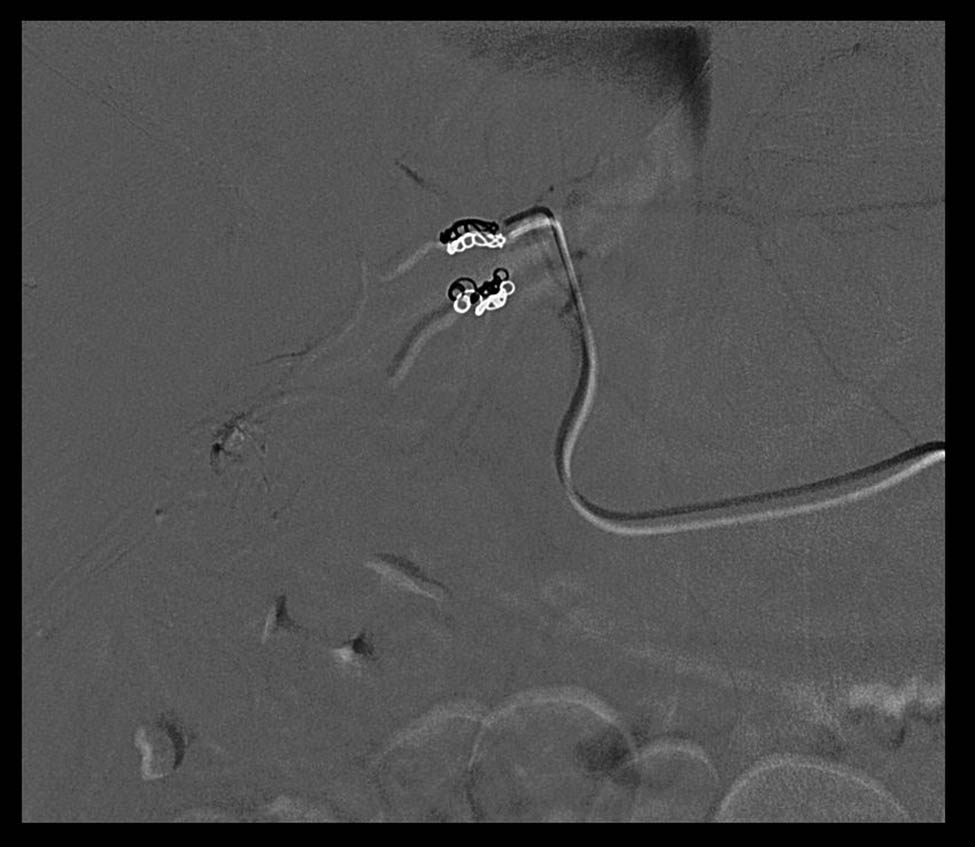

The arterial afferents of this lesion are embolized and metal microspirals are positioned, so that at the final check the lesion appears to be very well devascularized (Figure 3).

Metal microspirals and devascularizated lesion.